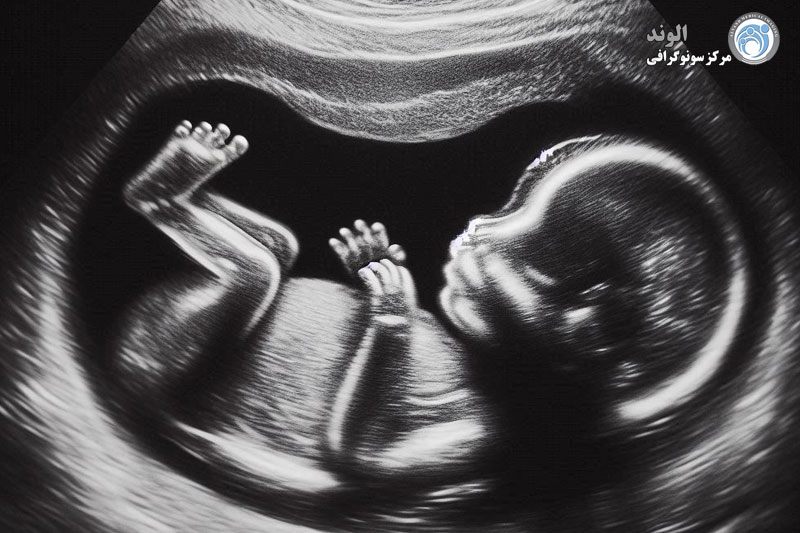

سونوگرافی اغلب در دوران بارداری زنان انجام می شود تا اطمینان حاصل شود که جنین به درستی رشد می کند. پزشکان همچنین ممکن است برای کمک به تشخیص مشکلات مربوط به موارد زیر، سونوگرافی تجویز کنند:

سونوگرافی بارداری: یکی از پرکاربردترین انواع سونوگرافی در مراکز پزشکی، سونوگرافی بارداری است که برای بررسی وضعیت جنین و سلامت مادر انجام می‌شود. این نوع سونوگرافی به‌ویژه در مراحل مختلف بارداری برای بررسی رشد جنین و تشخیص ناهنجاری‌های احتمالی مورد استفاده قرار می‌گیرد. در مرکز سونوگرافی الوند، این خدمات به صورت شبانه‌روزی و با دقت بالا انجام می‌شود.